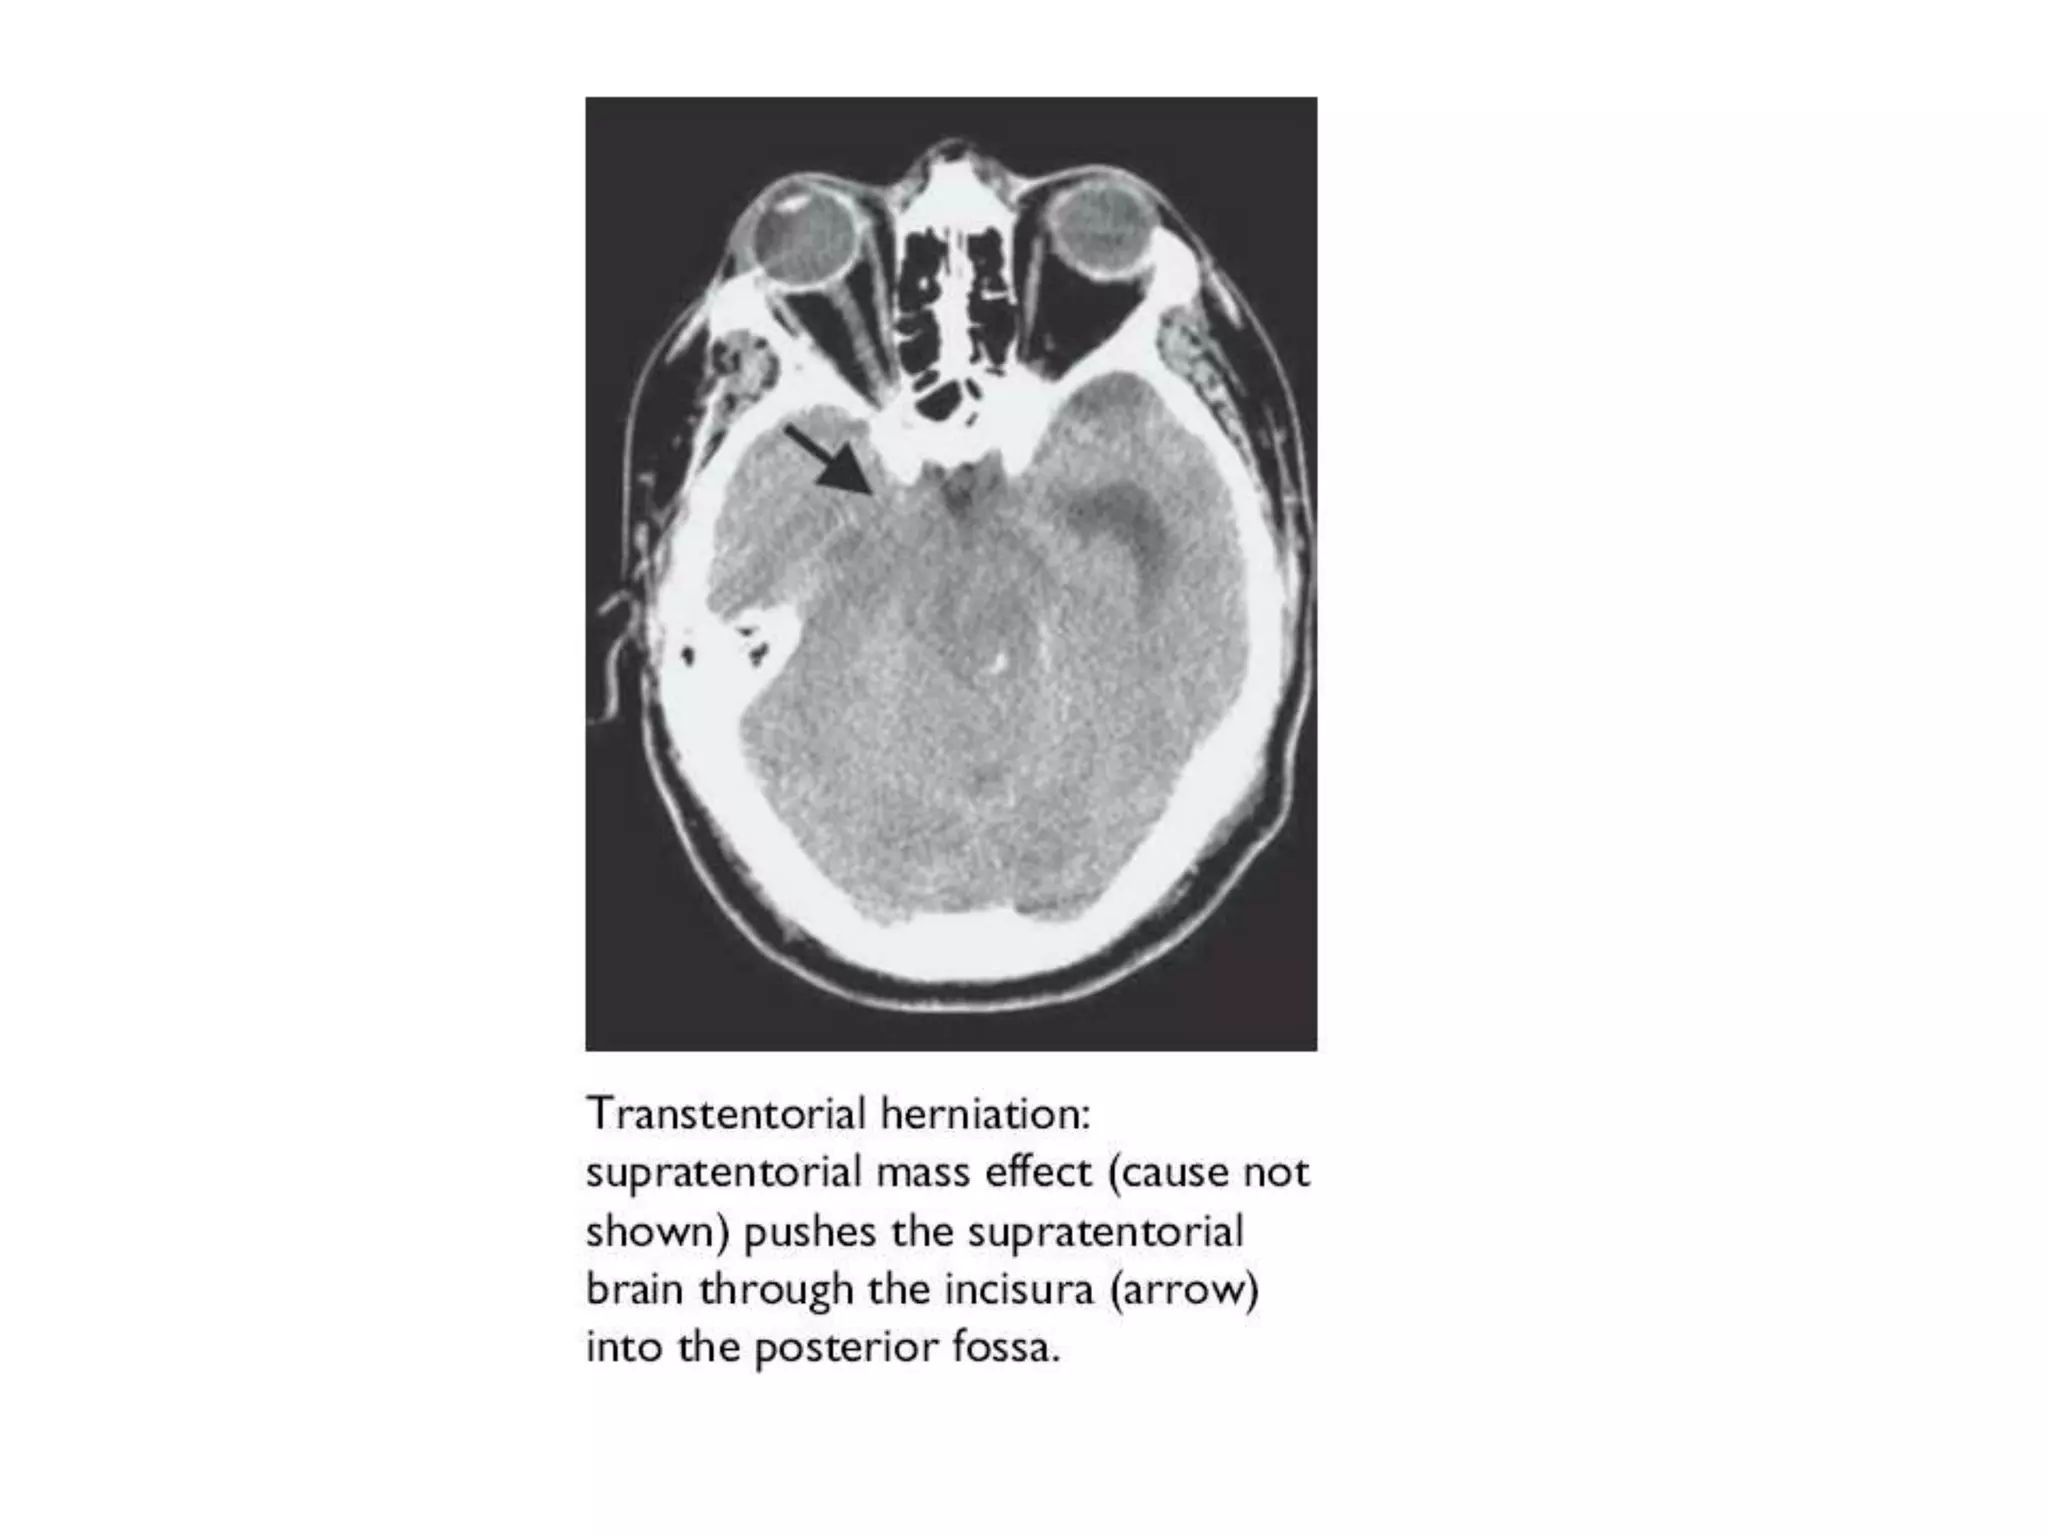

Central herniation In centralherniation, the diencephalon and parts of the temporal lobes of both of the cerebral hemispheres are squeezed through a notch in the tentorium cerebelli. Transtentorial herniation can occur when the brain moves either up or down across the tentorium, called ascending and descending transtentorial herniation respectively; however descending herniation is much more common.

Downward herniation canstretch branches of the basilar artery (pontine arteries), causing them to tear and bleed, known as a Duret hemorrhage. The result is usually fatal. Radiographically, downward herniation is characterized by obliteration of the suprasellar cistern from temporal lobe herniation into the tentorial hiatus with associated compression on the cerebral peduncles. Upwards herniation, on the other hand, can be radiographically characterized by obliteration of the quadrigeminal cistern. Intracranial hypotension syndrome has been known to mimic downwards transtentorial herniation.